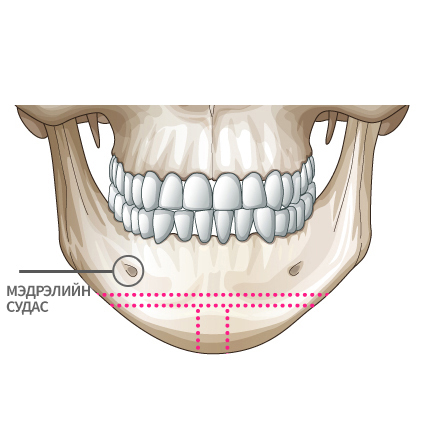

Mini V-line мэс заслын арга

Мэдрэлийн судаснаас зайлсхийж, эрүүний төгсгөлд зүсэлт хийнэ.

Ясны гол хэсгээс тайралт хийж авна.

Зүсэлт хийгдсэн эрүүний хоёр талыг нийлүүлнэ.

Эрүүний ясыг нийлүүлж тогтоож өгнө.

Хоёр хажуу талд товойж харагдах ясны хэсгийг тайрна.